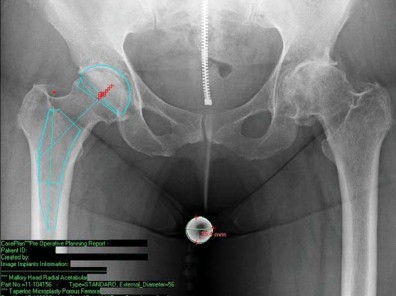

تُعد الأشعة السينية هي الأداة التشخيصية الأكثر أهمية. تُظهر الأشعة السينية مدى تآكل الغضروف، وتلف العظام، ووجود النتوءات العظمية (العظمية)، والتغيرات في بنية المفصل. يمكن أن تساعد هذه الصور في تأكيد تشخيص التهاب المفاصل أو غيره من الحالات التي تؤثر على الورك.

* التصوير المقطعي المحوسب (CT scan): يقدم صورًا مقطعية للعظام بتفاصيل عالية، وهو مفيد لتقييم التشوهات العظمية المعقدة أو التخطيط الجراحي الدقيق.

الزرعة نظام Taperloc Microplasty

يفضل الأستاذ الدكتور محمد هطيف استخدام نظام Taperloc® Microplasty من شركة Biomet (وارسو، إنديانا)، وهو أحد الخيارات المتاحة للزرعات الخالية من الأسمنت. يعتمد هذا النظام على تصميم إسفيني مخروطي وسطي-جانبي بدون ياقة، مصمم للتثبيت الذاتي والاستقرار الدوراني.

- المادة والتصميم: مصنوع من التيتانيوم (Ti-6AL-4V) ويتميز بطلاء مسامي رش بلازما محيطي قريب. تستخدم Biomet تقنية خاصة لتطبيق الطلاء المسامي بحيث لا يتم تسخين الزرعة بشكل كبير، مما يحافظ على مستويات عالية من مقاومة الإجهاد.

- الأحجام والتنوع: تتوفر السيقان في أحد عشر حجمًا، تتراوح أطوالها من 95 ملم إلى 130 ملم، وتزداد تدريجيًا جانبيًا بينما يظل الانحناء الأنسي ثابتًا. زاوية عنق-جذع 138 درجة، وهناك خياران للإزاحة: قياسي وجانبي.